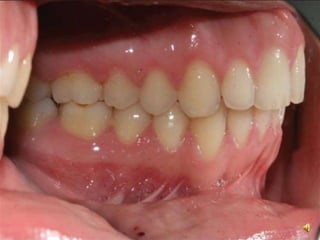

Angle Classification

• Class 1: Mesiobuccal cusp pf maxillary 1st molar occlude in

the buccal groove of mandibular 1st molar

• Canine relationship: The mesial incline of the maxillary

canine occludes with the distal incline of the mandibular

canine. The distal incline of the maxillary canine occludes with

the mesial incline of the mandibular first premolar

Angle Classification • Class1: Mesiobuccal cusp pf maxillary 1st molar occlude in the buccal groove of mandibular 1st molar • Canine relationship: The mesial incline of the maxillary canine occludes with the distal incline of the mandibular canine. The distal incline of the maxillary canine occludes with the mesial incline of the mandibular first premolar